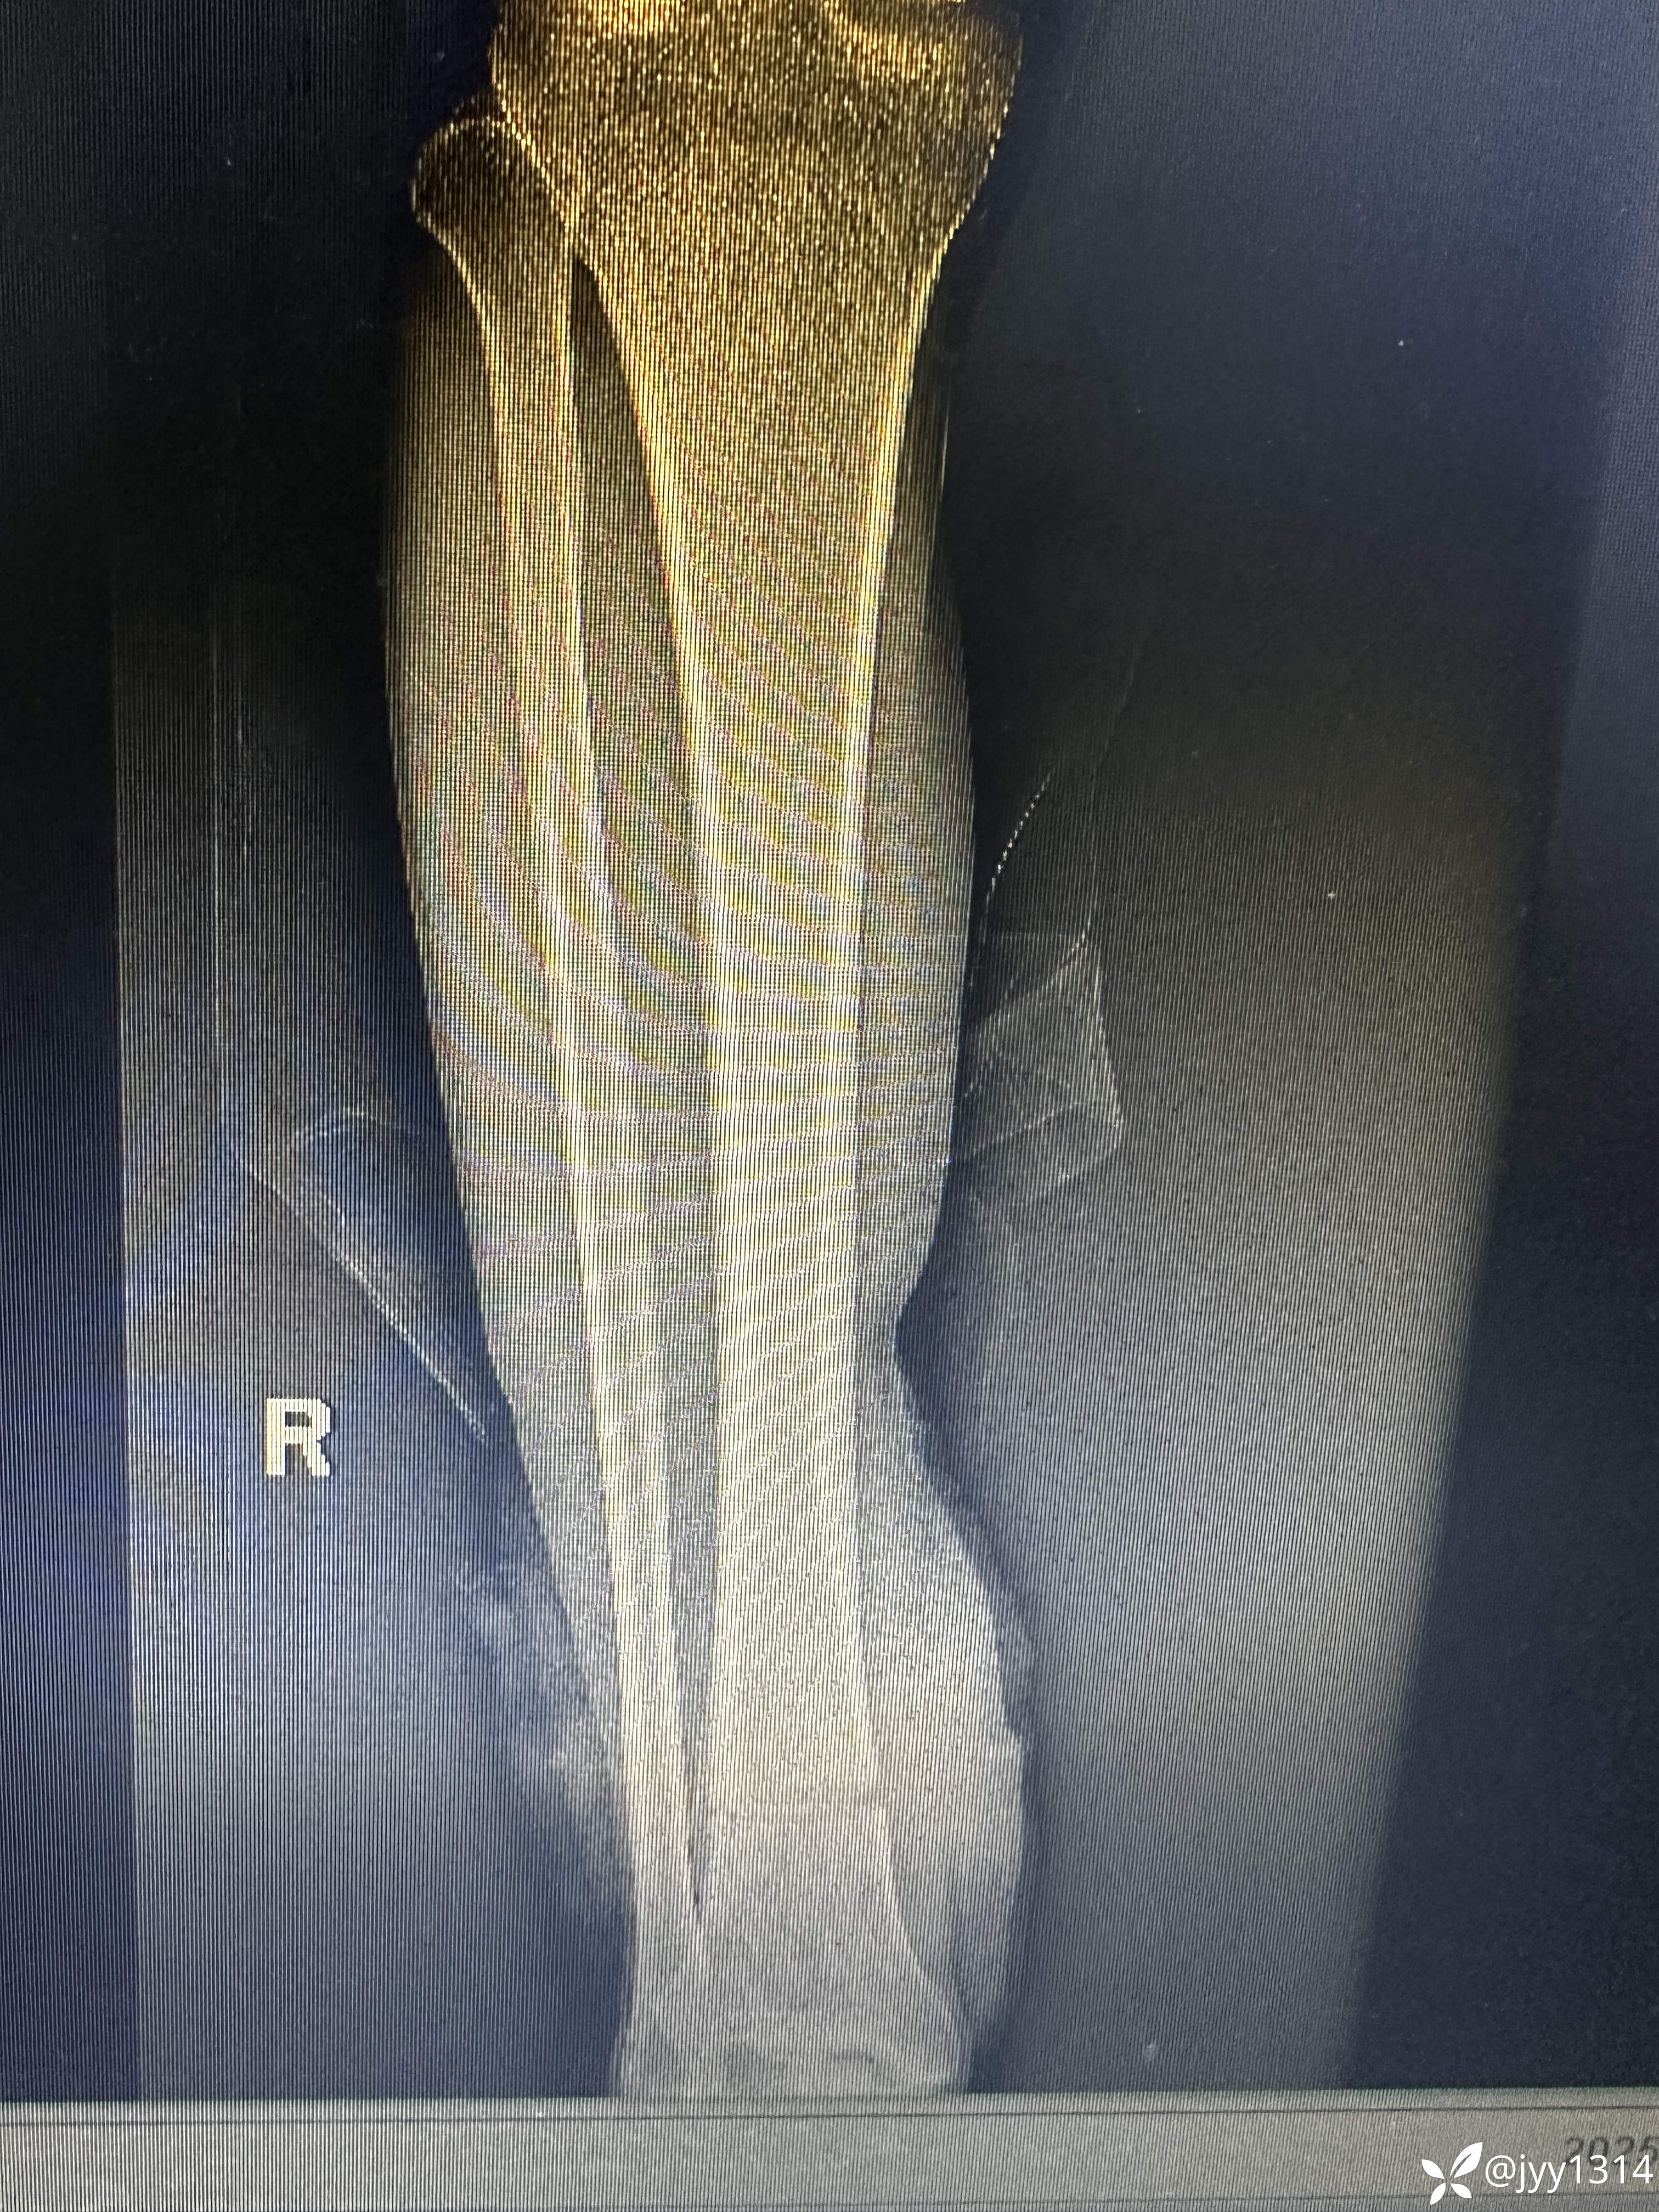

患者 男 63岁,右下肢锯伤1小时余。

患者1小时前与家人争执情绪激动使用电锯锯伤右小腿,致右下肢疼痛、出血,呼叫周围邻居送往我院。神志清,精神欠佳,表情痛苦,大、小未排。

神志清,精神欠佳,面色苍白,头部无压痛,胸部无压痛,心肺未闻及异常,腹软,无压痛,肝脾肋下未触及肿大。右小腿远端可见离断缺口,伤口周围出血不止,右下肢末端皮肤淤青。余肢体未见异常。